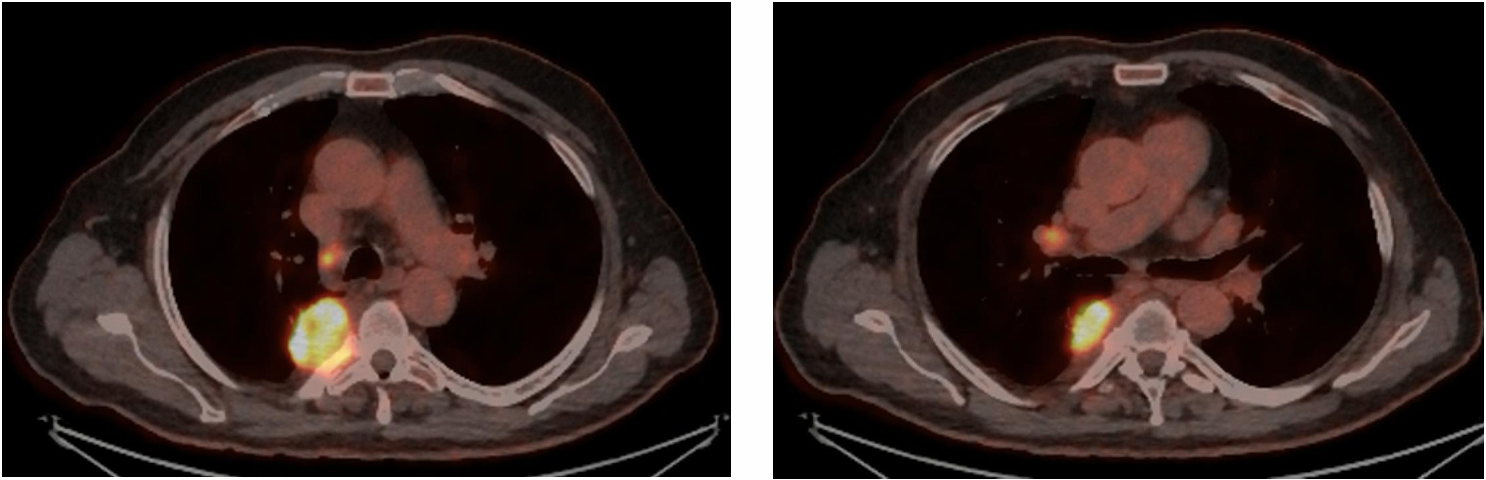

70岁男性,既往重度吸烟史(60包/年)。驱动基因阴性,PD-L1高表达(90%)。临床分期为cT1bN2a(4R组,Bulky/体积巨大)M0(IIIA期)。患者接受3个周期的卡铂+ 培美曲塞+抗PD-1抑制剂新辅助治疗。CT显示,巨大的4R组纵隔淋巴结达到部分缓解(PR)。淋巴结虽然缩小,但新辅助免疫治疗引发的局部炎症和组织纤维化,对后续纵隔淋巴结清扫术的精细度提出更高要求。